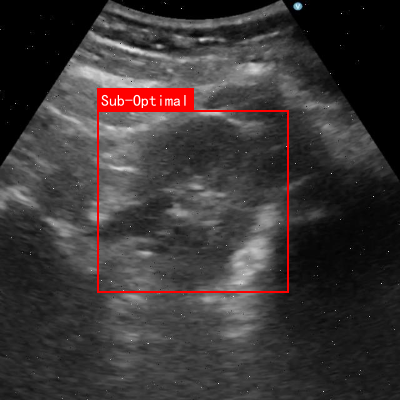

本数据集为肾脏超声图像质量评估与分类任务提供了专业的训练资源,采用CC BY 4.0许可协议,由qunshankj平台于2024年7月22日导出。该数据集共包含854张经过预处理的肾脏超声图像,所有图像均被调整为640x640像素的统一尺寸。数据集采用YOLOv8格式进行标注,包含两个主要类别:"Optimal"(最优质量)和"Sub-Optimal"(次优质量),分别代表高质量的肾脏超声图像和存在质量问题的图像。为增强模型的泛化能力,数据集应用了数据增强技术,包括50%概率的水平翻转以及0.16%像素的椒盐噪声添加。数据集被划分为训练集、验证集和测试集三部分,为模型训练和评估提供了完整的数据支持。这一数据集对于开发自动化的肾脏超声图像质量评估系统具有重要意义,可辅助医疗专业人员快速筛选出高质量的超声图像,提高诊断效率和准确性。